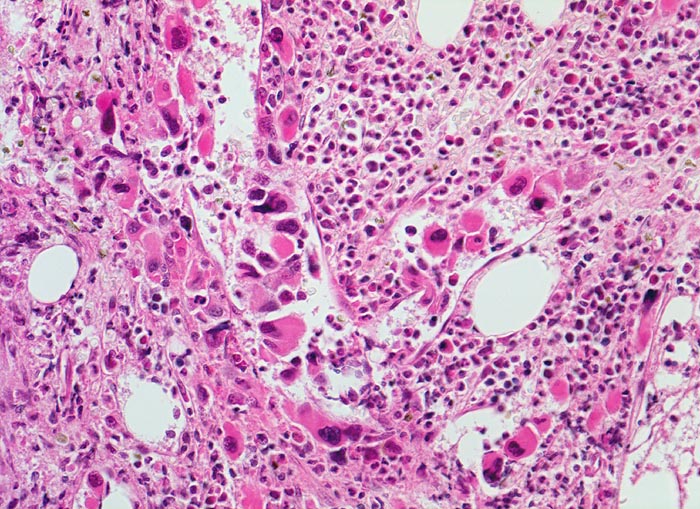

Die Erkrankung ist charakterisiert durch Knochenmarkfibrose, Hepato-Splenomegalie und extramedulläre Blutbildung. Diese findet sich am häufigsten in Leber und Milz, seltener in Lymphknoten, Nieren, Nebennieren, Dura mater, Gastrointestinaltrakt, Lunge, Mamma oder Haut. Blut und Knochenmark sind immer involviert. Die Krankheit entwickelt sich über ein initiales präfibrotisches Stadium mit hyperzellulärem Knochenmark zum fibrotischem Stadium (vorliegendes Präparat). Das fibrotische Stadium ist gekennzeichnet durch eine Vermehrung von Reticulin- und/oder Kollagenfasern und oft einer Knochenneubildung (=Osteomyelosklerose). Die Zellularität des Knochenmarks ist dann vermindert und dilatierte Marksinus enthalten intraluminale Blutbildungsherde. Es besteht eine auffallende Proliferation von Gruppen bildenden atypischen Megakaryozyten.

• Osteosklerose: verplumpte und breite Knochenbälkchen.

• Dilatierte Sinusoide mit intrasinusoidaler Blutbildung.

• Vermehrung von atypischen, in Gruppen liegenden Megakaryozyten mit abnorm lobulierten Kernen.

• Nacktkernige (zytoplasmaarme) und vergrösserte Megakaryozyten.

• Hyperplastische ausreifende Myelopoese.

• Hypoplastische Erythropoese.